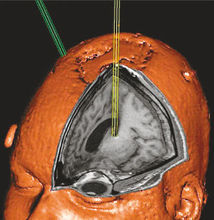

昏迷狀態長達6年之久的植物人大腦兩半球極度嚴重的損害或功能障礙所造成的自覺的思維活動能力的喪失,但間腦與腦幹的功能有充裕的保留,因此一些自主神經反射與運動反射都有保存,並可有正常的睡眠-覺醒周期.

在若干種瀰漫性腦損傷後可以出現暫時性的植物人狀態(vegetative state).持續超過4周以上的植物人狀態被人為地稱為持久的植物人狀態.持久的植物人狀態最常發生在嚴重的腦外傷或全面性缺氧(例如由於心臟停搏)之後,恢復意識的預後較差.

一旦植物人狀態持續超過數月,很少見有好轉,無人能完全恢復.處於持久植物人狀態中的成年人,大約有50%的機會能在頭部受傷後開始的6個月內重新恢復一定程度的意識對環境能有所反應.通常會發生永久性的腦功能障礙.過了半年以後,愈來愈少的病人能對周圍環境有任何系統性的感知.在醫院中發生心臟停搏後出現植物人狀態的病例中,只有10%~15%能恢復意識,在醫院外發生心臟停搏者能恢復意識的不超過5%.在腦外傷後處於持久植物人狀態的兒童中,大約60%在1年之內能恢復意識,但缺氧性腦損害的兒童病例的預後則與成人病例大致相同.只有極小一部分病例能在6個月以後有相當程度的意識恢復以致可以獨立照顧自己.